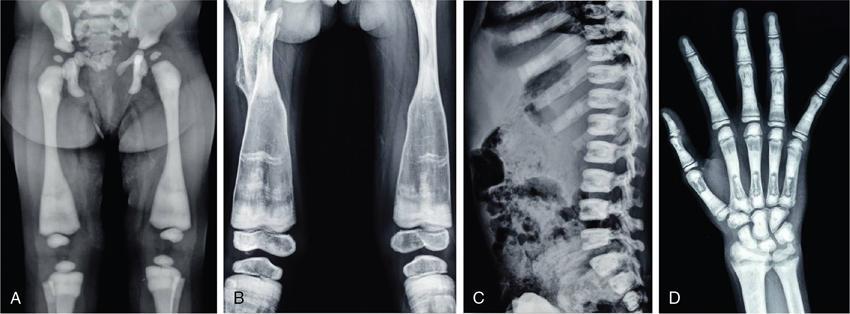

MISCELLANEOUS PAEDIATRIC RADIOGRAPHY – TECHNIQUES AND INTERPRETATION: SKELETAL SURVEY Padma V. Badhe The skeletal survey, generally performed in children, is a set of radiographs done in order to evaluate the entire skeleton. A skeletal survey, commonly used to evaluate skeletal dysplasias, acquired metabolic disorders and suspected child abuse, is still the key radiological investigation for the same. Hence, an explicit understanding of the technique along with the common disorders forms the basis of making a diagnosis in these paediatric pathologies. A skeletal survey is done for various skeletal dysplasias, non-accidental injury (battered baby syndrome) and suspected child abuse. It can also be done in cases of metabolic bone diseases, disseminated infections, multiple myeloma, eosinophilic granuloma. It is also used in evaluation of metastatic bone diseases and polyarticular arthropathy. Orthogonal views of the skull, spine, pelvis and one extremity are taken, preferable in standing position. For preterm babies/newborns, AP and lateral views of babygram may be taken. Projections: For skeletal dysplasias: Additional views: Both extremities may be taken if epiphyseal abnormalities and limb asymmetry is present. Focused views for specific pathologies may be taken. When a diagnosis remains uncertain, 1 year follow up is usually recommended. For preterm babies/newborns: AP and lateral views of babygram may be taken with additional specific views for extremities. For suspected non-accidental injury (NAI): AP and oblique view of chest is taken for better evaluation of the ribs. AP view of abdomen with pelvis. Both upper and lower limbs are evaluated. In lower limbs, two projections in AP and lateral (one with both femur including hip and knee joints; and another for foot and ankle) is taken. AP and lateral views of whole spine, skull. Oblique view of hands. A babygram should be avoided in cases of NAI, as subtle fractures are easily missed. Proper legal documentation while taking the views is very important and ideally two health care professionals must be present. For metabolic disorders: entire skeletal survey is usually not required. Specific views of hands, knees and spine may be taken with additional views depending on the suspected pathology. Centring point: Varies according to the part being examined. Angulation, collimation and orientation: Varies according to the part being examined. Images must be well collimated to obtain lower radiation dose. Detector size: Varies according to the part being examined: 8″ × 10″, 10″ × 12″, 11″ × 14″. Exposure: Ideally high kVp images are taken to reduce radiation dose. But in suspected NAI, low kVp/high mA images are recommended to better demonstrate findings. SID (Source Image Distance):100 cm Grid: Grids are not routinely used to image spine, pelvis, skull and abdomen in children. Radiation dosage: 0.3–3 mSv Essential image characteristics: Adequate spatial resolution, high signal to noise ratio, low kVp (50–70) for high contrast should be done. Excellent bone and soft tissue details are required. The presentation of skeletal dysplasia can range anywhere from minimal stunting of growth and bowing of limbs to severe dwarfism and multiple fractures. Knowledge of the commonly encountered dysplasias with an approach to arrive at a diagnosis is vital in any Radiologist’s practice The following flow chart summarizes the classification of important skeletal dysplasia: The following table summarizes the various dysplasias affecting the axial skeleton: TABLE 7.5.1.1 The following flow chart summarizes the working approach to skeletal dysplasias: Osteopetrosis (Albers-Schonberg disease/Marble bone disease) (Fig 7.5.1.1): Osteopetrosis clinically presents with anaemia/thrombocytopenia or cranial nerve compression. Radiological features include generalized increase in bone density with loss of medullary space. However, cortico-medullary appreciation with cortical thinning is also rarely seen. Bone within bone appearance with Erlenmeyer flask deformity is also noted. Pyknodysostosis (Figs. 7.5.1.2 and 7.5.1.3): patient presents with short stature. Unlike osteopetrosis, there is no anaemia. Radiographs show generalized increase in bone density with preserved medullary canal. There is mandibular hypoplasia with obtuse angle. Acro-osteolysis is also a feature. Dental caries with osteomyelitis of the jaw may be seen. Sclerosing dysplasia presenting as wavy undulating new bone formation. Usually monomelic, lower limb and along one side. The classic appearance is described as Dripping candle Wax sign. It is a Sclerosing dysplasia with radiological features of symmetric juxta-articular involvement in epimetaphyseal region. They are 1–10 mm in diameter and uniform in size. No metabolic activity is seen on bone scans. This skeletal dysplasia shows diffuse decrease in bone density with paper-thin cortex. Fractures heal in normal time but shows callus with poorly cellular matrix. Wormian bones and enlarged sinuses may be seen. Codfish vertebra (Biconcave vertebra) may be seen. Metaphyseal corner fractures are not seen in osteogenesis imperfecta that helps to differentiate it from battered baby syndrome. There are four types of OI out of which type one is most common (Figs. 7.5.1.6 and 7.5.1.7). The radiological features of MPS include Osteopenia and Universal platyspondyly. The intervertebral disc spaces are maintained. Proximal pointed metacarpals is an important radiological finding. Hurler’s syndrome show anteroinferior beaking with short and wide metacarpals. Varus deformity of humerus is characteristically seen in Hurler’s syndrome (Fig. 7.5.1.8). Mental retardation & corneal clouding is seen in Hurler’s syndrome whereas these Hunter’s disease has normal intelligence with no corneal clouding. Morquio’s syndrome shows central beaking (Fig 7.5.1.9). This skeletal dysplasia shows normal bone density with rhizomelic limb shortening and normal trunk. Narrowing of spinal canal is classically seen with decrease in the Interpedicular distance caudally. Other radiological features include trident hand (separation of middle & third fingers), Champagne glass pelvis (short, flat ilia and small sciatic notch), bullet nose vertebra and overexpansion of skull with narrow foramen magnum (Fig. 7.5.1.10). This skeletal dysplasia is characterized by normal bone density with dwarfism and normal craniofacial skeleton. The interpedicular distance is normal. There is severe platyspondyly with anterior tonguing (disappears at older age). Other radiological features include increased disc space, short stubby metacarpals, small irregular epiphysis and widened metaphysis. Anterior tonguing is a feature of Pseudoachondroplasia. This form of skeletal dysplasia involves the spine and epiphyses (Fig. 7.5.1.11). There is normal bone density with rhizomelia. Spine and Pelvis can be involved. Premature osteoarthritis can be seen. The other characteristic features include Platyspondyly and small irregular epiphysis. There are two forms Spondyloepiphyseal dysplasia Congenital and Spondyloepiphyseal dysplasia Tarda. Spondyloepiphyseal dysplasia Congenita is Autosomal dominant and shows pear-shaped vertebrae. Spondyloepiphyseal dysplasia Tarda is X Linked recessive with heaped up vertebrae. It has two forms. The first form is Conradi Hunermann syndrome which is autosomal dominant characterized by asymmetric limb shortening with metaphyseal flaring (Fig. 7.5.1.12). The Autosomal recessive form is Fatal in first few years. Rickets: Rickets refers to deficient mineralization of the growth plate in the paediatric population due to deficiency of vitamin D. In an immature skeleton, there is abnormal mineralization at the zone of provisional calcification in the metaphysis due to osteoid deposition resulting in widening of the growth plate. The features of rickets include fraying, splaying and cupping (Fig. 7.5.1.13). Fraying denotes indistinct margins of the metaphysis whereas splaying denotes widening of metaphyseal ends. Term ‘Cupping’ is used for increased concavity of the metaphysis. These findings are typically seen involving areas of active growth (e.g. distal femur and proximal tibia in the knee) Bowing is a result of associated osteomalacia leading to weakening of weight-bearing lower limb bones. Other bone deformities such as genu valga, genu varum, protrusio acetabuli can also be seen. The lower ribs may also be drawn inwards inferiorly by the attachment of the diaphragm this is called Harrison’s sulcus. Scurvy: Scurvy is a result of dietary deficiency of Vitamin C (ascorbic acid). The classic presentation is that of a patient with an increased bleeding tendency and osteopenia with poor wound healing. Features of scurvy include generalized osteopenia with cortical thinning termed as ‘pencil-point’ cortex. Other radiological findings include the periosteal reaction due to subperiosteal haemorrhage. Expansion of the costochondral junctions occurs forming scorbutic rosary. Bleeding into the joint spaces may result in hemarthrosis. Circular, opaque radiologic shadow surrounding epiphyseal centres of ossification may result from bleeding (Wimberger ring sign) (Fig. 7.5.1.14). Frankel line may be seen. It represents dense zone of provisional calcification. Lucent metaphyseal band is seen underlying Frankel line called as Trümmerfeld zone. Metaphyseal spurs may be seen that result in cupping of the metaphysis (Pelkin spur). Pelkin fracture (metaphyseal corner fracture) can also be seen. Images obtained must be of good resolution with adequate bone and soft tissue details. Additional views: They have already been described in positioning. CT Brain in can be done in cases of NAI to look for subdural hematomas. A skeletal survey is the first-line imaging modality for evaluation of skeletal dysplasia, nonaccidental injury and metabolic bone diseases. The skeletal survey must be tailored according to the respective indication. It helps to characterize syndromic patterns in skeletal dysplasias, with evaluation of complications. In cases of diagnostic dilemmas, additional focused view and occasionally yearly follow-up is recommended. A high index of suspicion is needed in utilizing skeletal survey as a diagnostic modality in NAI. At the same time, one must also remember the legal and social implications of making this diagnosis. BABYGRAM Babygram is a colloquial term used for a radiograph of the whole body of a newborn or just the chest and abdomen (thoracoabdominal babygram) on a single image. As the name suggests it is a rather non-targeted study. It is most commonly requested after line placement. Evaluation of skeletal abnormalities in a deceased foetus is typically performed using anteroposterior and lateral views of a babygram. It helps in pointing out skeletal causes of death in stillborn or dead foetuses. This will help the treating physician and parents understand the reason for baby’s death. This will also help in future genetic counselling of the couple. Sometimes chest or abdominal radiographs of the baby are requested but due to radiographers error or inexperience with small babies, there is inclusion of the region not to be assessed leading to a false babygram. Babygram is most frequently done after line placement in neonates, to view the position of the umbilical vein or artery catheter and to confirm appropriate placement. It is a useful modality in skeletal dysplasias (Fig. 7.5.1.15) like osteogenesis imperfecta, thanatophoric dysplasia and chondrodysplasia punctata. It can also be used for skeletal deformations probably caused by foetus akinesia and in cases of Caudal regression syndrome. In stillborn foetuses, it is used for evaluation of skeletal dysplasias prior to an autopsy (Fig. 7.5.1.16). It is also used in screening for surfactant deficiency and in cases of Necrotizing Enterocolitis in preterm babies where it can help to see the bowel dilatation, intramural and portal venous gas. It can be done in aneuploidies like trisomy 18 and in cases of sudden infantile death syndrome. All the essential equipment and room need to be prepared including the exposure factor. This should be done prior to placing the baby on the table to prevent any neonatal heat loss. Ensure that the baby is correctly identified. Give brief explanation to the patient’s parents regarding the procedure, its risks and benefits. Ensure that the accompanying relative is not pregnant (if female). Parents/guardians/nurses should be instructed to hold the baby with arms above the head and legs straight down. Sandbags/tapes can be used to immobilize the baby. Avoid taking the radiograph when baby is crying. Normal appearance: The endotracheal tube should lie in the lower third of trachea, distance can vary with position of baby’s head. Umbilical artery catheter has an inferior dip along the internal iliac artery, which then turns superiorly along the aorta. The tip should lie in the mid-thoracic aorta (T6–T10) or lower (L3–L4) away from aortic branches to prevent any thrombosis. Umbilical venous catheter does not have the inferior curvature, but rather a posterolateral angulation to the right near the liver through the ductus venosus. The tip should lie in the superior IVC or right atrium at T8/T9 vertebral level (Fig. 7.5.1.17). Portal venous gas may be seen initially after insertion. In a stillborn foetus, the approximate gestation age of the foetus and corresponding ossification centres must be known. In early gestation, the lack of appearance of an ossification centre may be mistaken for skeletal dysplasia. Both chest and abdomen should be included. In a rotated patient, the distance between the spinous process to medial end of clavicles will be asymmetric. The medial end of clavicle should overlap the lung apex, if above, suggests lordotic image. Motion artefacts to be reduced as much as possible. A crying neonate may result in an expiratory film, and hence must be evaluated accordingly. In evaluation of skeletal dysplasias in the newborn, additional views of skull and hand have to be obtained. Baby gram is a useful diagnostic investigation for position of the paediatric umbilical catheters. It helps in general survey in skeletal dysplasia (Fig. 7.5.1.18). It is a simple, effective study in deceased foetus for diagnosis and further counselling, sometimes obviating the need for an autopsy. As baby gram is a non-targeted study, it increases the dose of radiation for the baby. As the exposure settings remain same for the entire body of the baby, the quality of the image decreases. This increases the chances of missing subtle findings. The babygram in a neonate is currently used to localize umbilical catheters. In stillborn fetuses, it is still an important study for documenting and confirming skeletal dysplasias. Understanding the normal appearance as per gestation age and patterns of various common skeletal dysplasias is essential for evaluation. Being a non-targeted study, it should not be used as an alternative study to evaluate the chest or abdomen considering radiation exposure and poorer image quality. INVERTOGRAM Invertogram was first described by Wangensteen and Rice in 1930. It was used as a first investigation to be ordered in evaluation of infants with clinically diagnosed or suspected Anorectal Malformation (ARM). ARM is a serious but surgically treatable congenital malformation with approximate incidence of 1 in 5000 live births. Though the diagnosis of this condition is based on clinical history and physical examination, imaging plays an important role in deciding the type of ARM, and associated complications to aid in management. International classification of anorectal malformations is as follows. Syndromic association is seen as a part of VACTERL defects, trisomy 21 13 and 18, Klippel Feil syndrome, cat eye syndrome etc. The main indication of Invertogram is to evaluate anorectal malformation in a neonate. A radio-opaque marker is placed over the external anal opening. Infant is held inverted by holding both thighs, maintaining this posture for at least 5 minutes before taking an X-ray in true lateral position (Fig. 7.5.1.19). Exposure is made during inspiration. The Invertogram should ideally be done 24 hours after birth as, the rectal gas may not reach the terminal segment if study is done too early. Pubo-coccygeal line (PCL) is drawn from upper border of pubic symphysis (which corresponds to centre of pubic bone on lateral X-ray) to sacrococcygeal junction. I point is the inferior most point of ischial ossification centre. A line which is drawn parallel to PC line passing through the I point is called I line. ‘A’ point is represented by marker placed at anal pit. The position of rectal pouch gas shadow is observed with respect to these lines and appropriate diagnosis is made (Fig. 7.5.1.21). A diagnosis of high ARM is made when gas shadow of rectal pouch is cranial to PCL. If rectal pouch gas shadow is in between PCL and I line, it is called as intermediate ARM and if it is caudal to I line, it is diagnosed as low ARM. Gas in urinary bladder or vagina or beaking of gas shadow of rectal pouch indicates fistula into one of these sites. Associated congenital abnormalities like spinal defects are also looked for in the invertogram (Fig. 7.5.1.22). Invertogram done too early (less than 24 hours) may not demonstrate rectal gas. Meconium plugging the terminal segment gives false position of the rectal gas. Positioning can cause discomfort to child and an irritated crying child actively contracts the sphincter muscles, pushing the gas shadow higher. Rectum may be pulled cephalad due to gravity in inverted position. The rectal gas may escape through an associated fistula. Erroneous interpretation can also occur due to sacral anomalies and when gas in vaginal cavity is misinterpreted as distal rectal gas. Both ischial bones should superimpose and terminal blind loop should be well distended. It is an easily available modality and can be done quickly, does not require additional equipment. It has lesser radiation dose as compared to CT invertogram. It provides a rough guide as to the type of ARM and decides management. Higher localization of obstruction due to various causes like meconium plugging, imaging done too early etc. as described above in pitfalls. It is more uncomfortable to the baby as compared to the prone cross-table lateral view, and a crying baby contracts the puborectalis leading to erroneous results. K. L. Narasimharao et al. modified the technique and proposed cross-table lateral view for evaluation of infants with ARM’s which has shown equal or better information and has now replaced invertogram (Fig. 7.5.1.23). Prone cross-table lateral view is considered equivalent or even better in determining the level of anomaly. Positioning is in this view is prone in genupectoral position (at least for 3 minutes). It is taken in true lateral and during inspiration. The lines used to delineate types of ARM is essentially the same as in an invertogram. It is preferred over invertogram as relatively easy positioning of the infant and less discomfort allows for better cooperation of neonate during the study. It also eliminates the effect of gravity. ARM with fistula is better delineated as, in an invertogram, fistula/gas is at the highest level and gas may escape through it. CT invertogram is another modality that delineates anatomy better but is rarely used. In the era of cross-section imaging, MRI and USG have opened new modalities for accurate diagnosis of ARM, but invertogram being readily available, inexpensive, quick and cost-effective is used as first investigation for evaluating a patient with suspected or confirmed case of ARM. Cross-table lateral view has replaced invertograms as it is more patient-friendly and equally effective. UPPER GASTROINTESTINAL SERIES Rushit S. Shah An upper gastrointestinal (GI) study is a radiographic examination of the GI tract from the pharynx to the ligament of Treitz after oral administration of contrast agent. The use of upper GI studies is gradually declining with the increasing availability of paediatric endoscopy and the challenge for the modern radiologist to work in conjunction with the surgeon and gastroenterologist to select the right patients for an upper GI series. However, the upper GI series remains the key for demonstrating many anatomical abnormalities. The upper GI series is also useful in evaluating gastro-oesophageal reflux in conjunction with 24 pH monitoring. The upper GI examination is useful in evaluating many conditions including but not limited to: